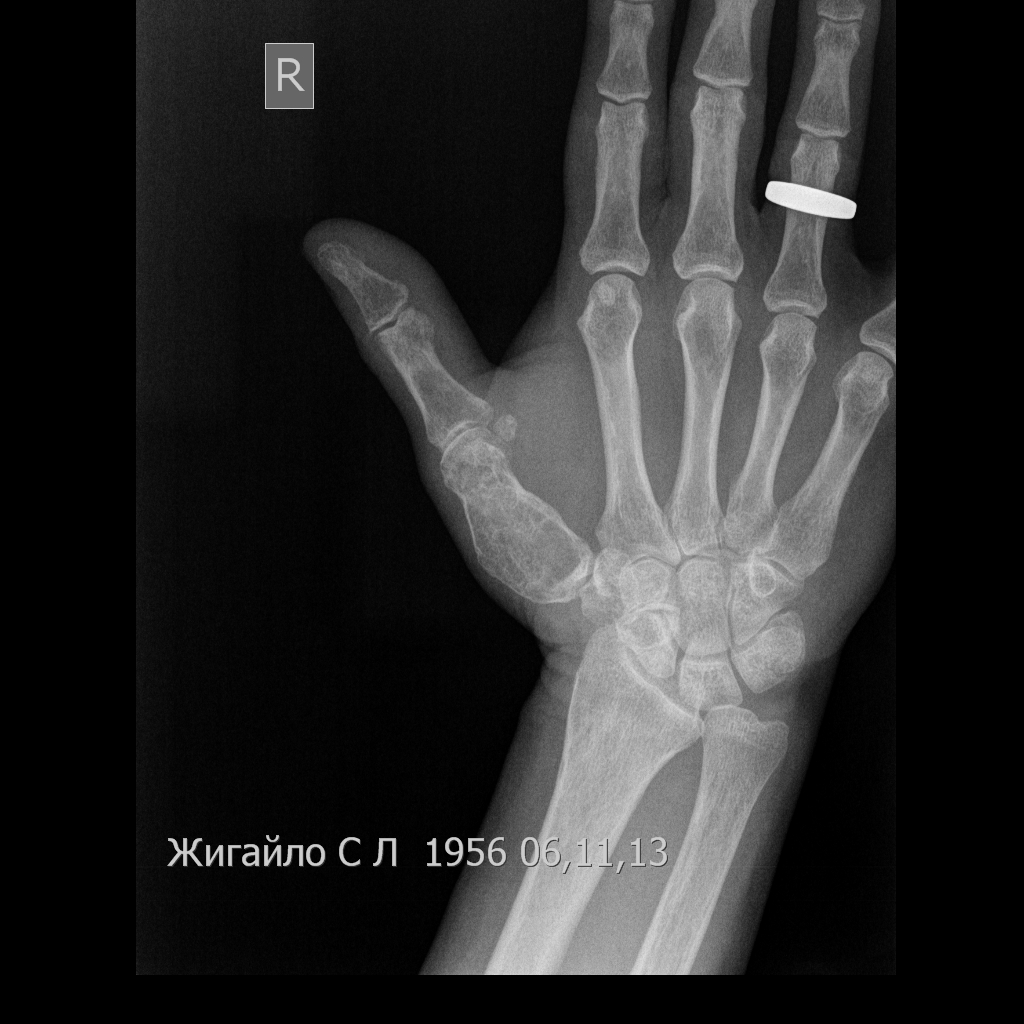

[Ortho] Опухоль 1 пястной кости.

пациентки 51г вр.дерматолог.Боли около года.Рентгенографию сделала

первый раз.